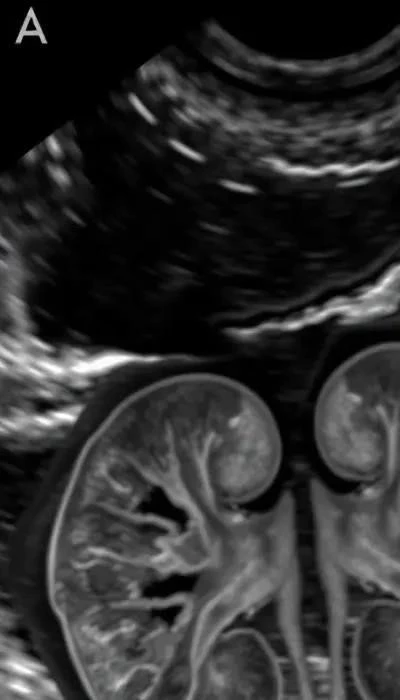

Порода играет важную роль: чаще всего поликистоз встречается у персидских кошек и других пород с длинной шерстью. Ранняя диагностика с помощью УЗИ может помочь выявить заболевание на ранней стадии и замедлить его прогрессирование. К сожалению, полного излечения не существует.

Диагностика болезней почек – важный этап для определения причины заболевания и назначения эффективного лечения. Основными методами диагностики являются анализ мочи, биохимический анализ крови, ультразвуковое исследование (УЗИ) почек и рентгенография почек.

Анализ мочи позволяет оценить концентрационную способность почек, наличие белка, крови и других патологических элементов. Биохимический анализ крови оценивает уровень креатинина и мочевины – основных показателей почечной функции. УЗИ почек визуализирует структуру почек, позволяя выявить кисты, камни и другие структурные изменения. Рентгенография может помочь в выявлении камней в почках.